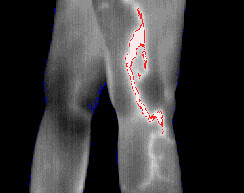

Varicose Vein (DITI).